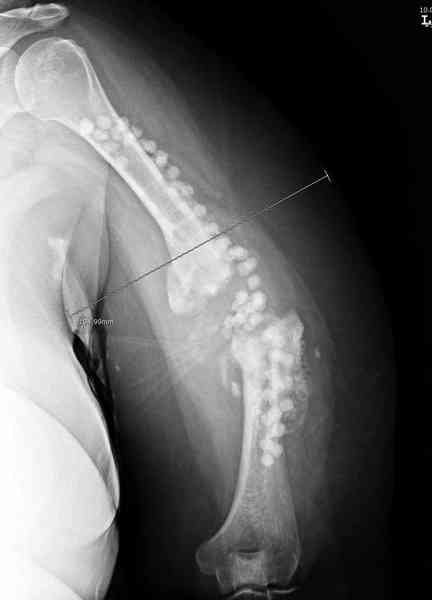

А для стимулирования мы применили массу из состава: OP1 с

деминерализованной костью, добавив к ним еще красную часть,

приготовленную из крови больной. Взятая перед операцией кровь в

количестве 80 мл провели через центрифугу и без сывороточной части

красную матрицу добавили к остальным.

С такой массой наверное ложный сустав "over killed", но надеюсь,

что-то из них при такой фиксации окажет стимулирующее действие.